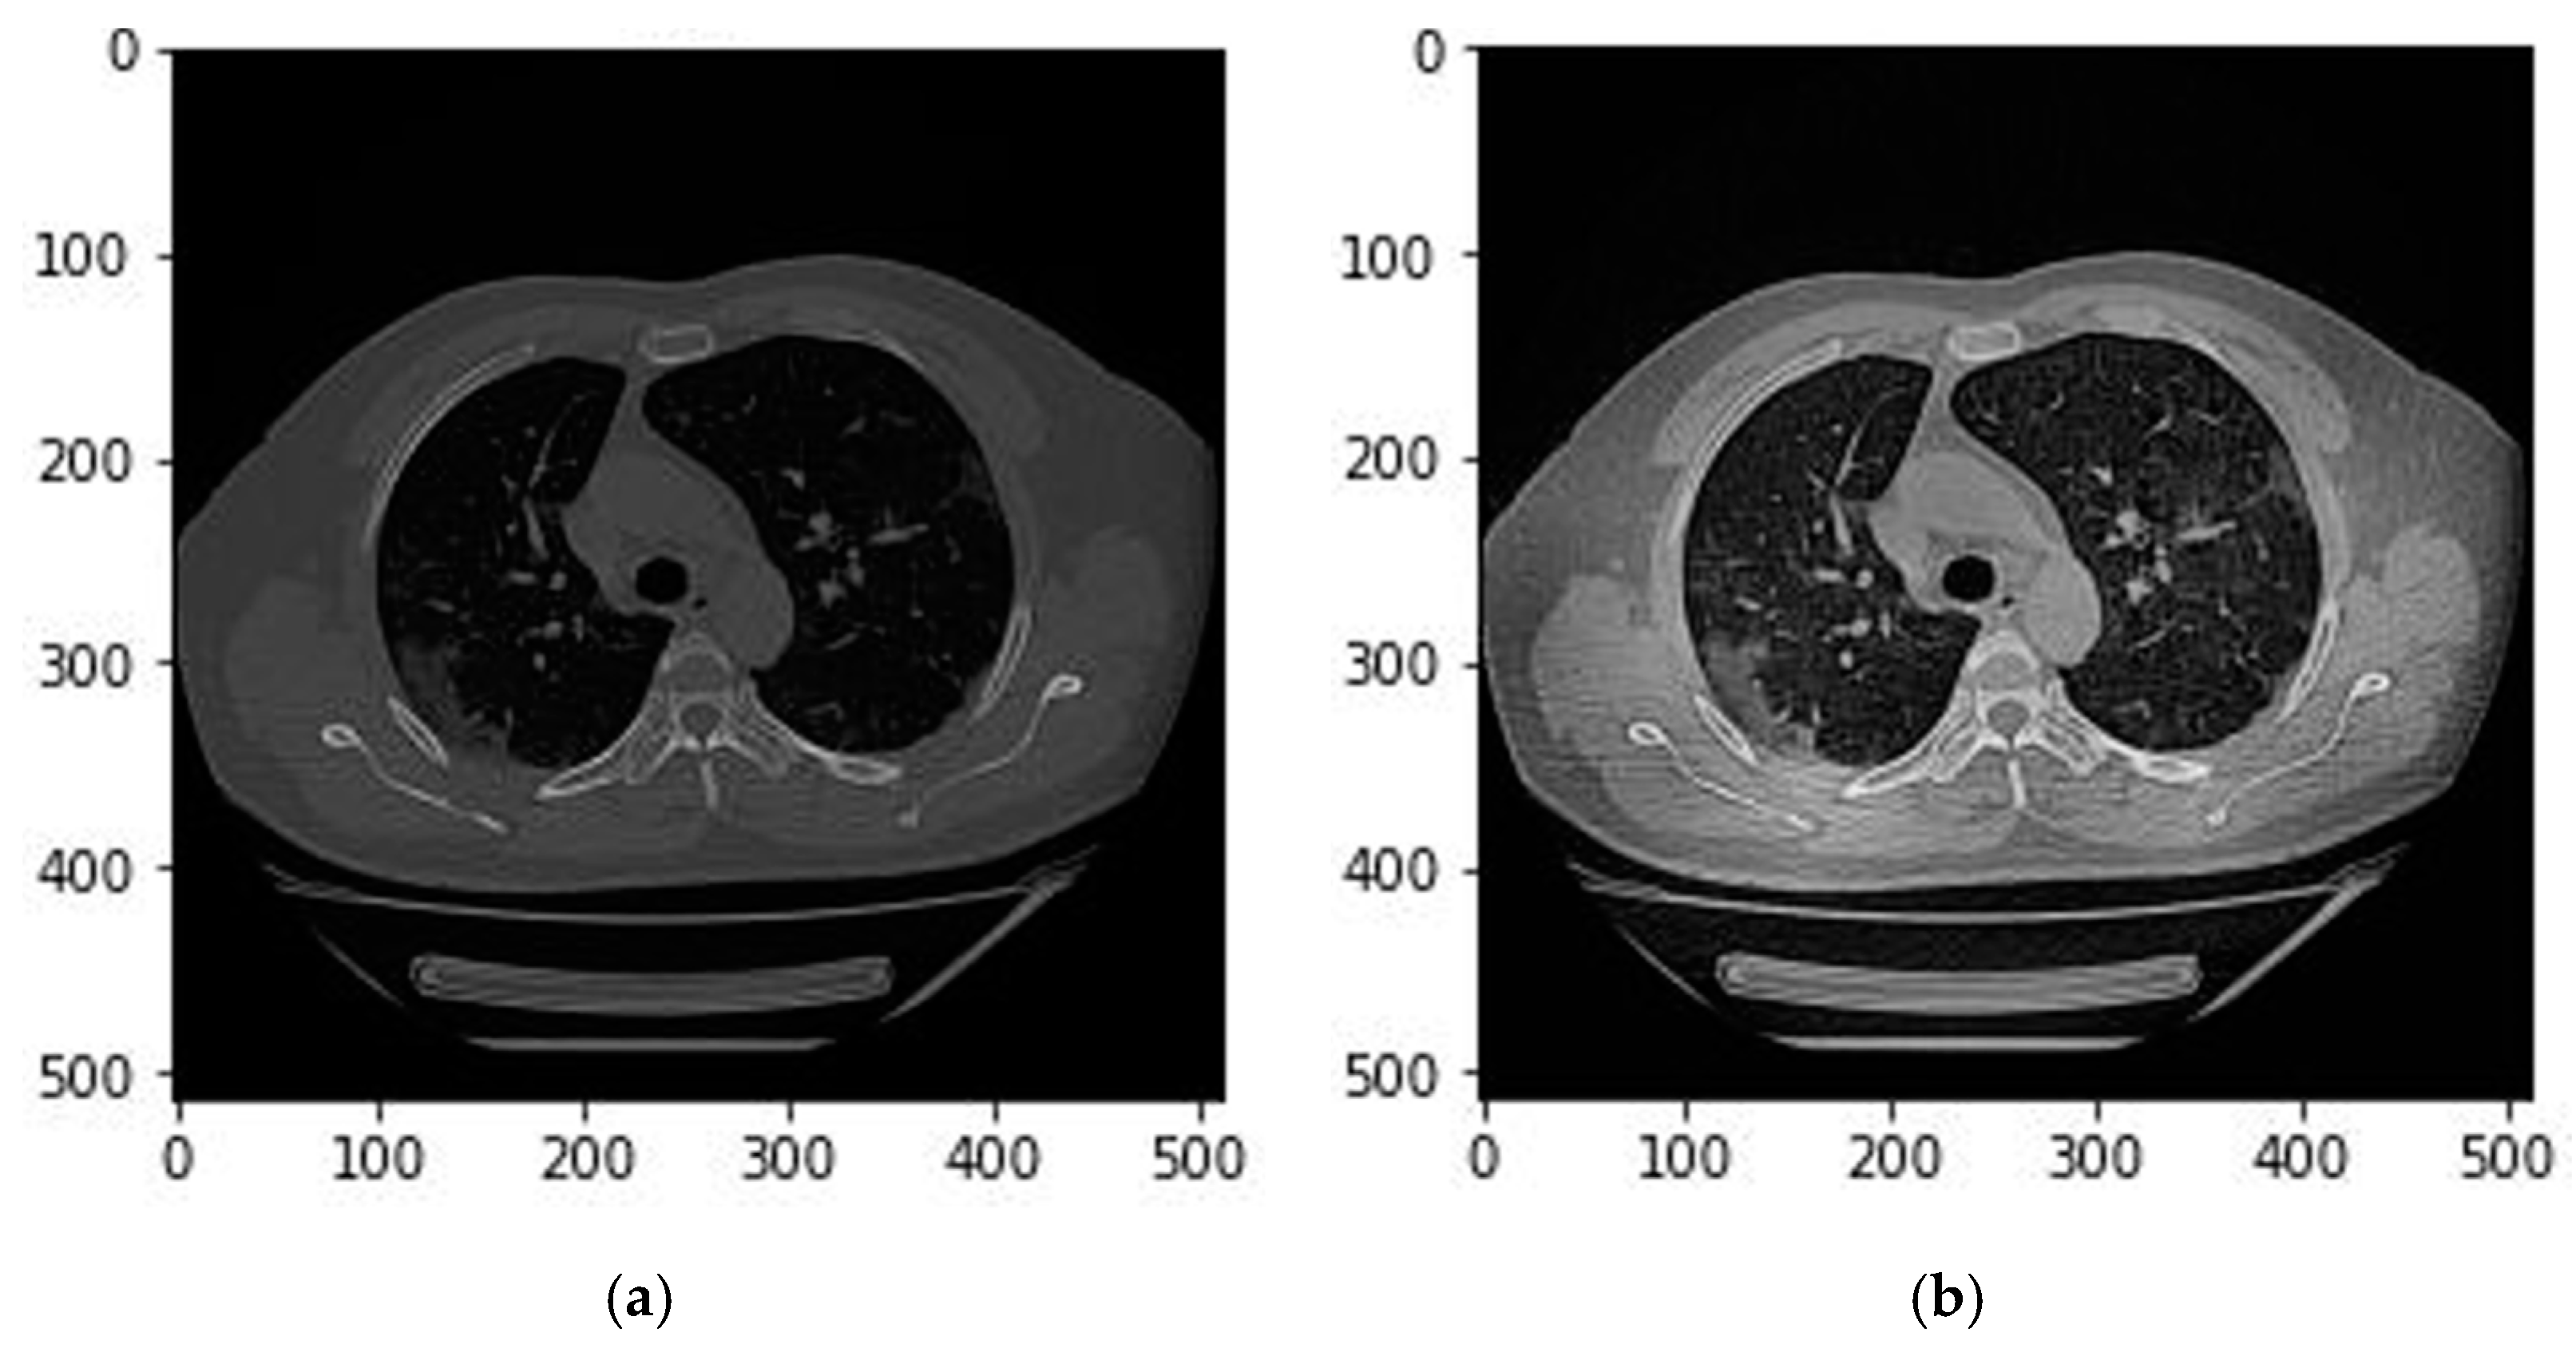

2.2. Image Preprocessing

2.3.1. Lung Segmentation